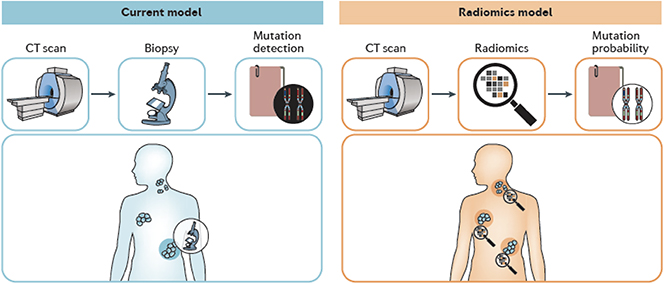

The fundamental research on the physics of elementary particles and nature's fundamental forces led to numerous spin-offs and has tremendously helped human well-being and health. Prime examples include the electron-based generation of x-rays for medical imaging, the use of electrical shocks for treatment of heart arrhythmia, the exploitation of particle's spin momenta for spin tomography (NMR) of patients, and the application of particle beams for cancer treatment. Tens of thousands of lives are saved every year from the use of those and other physical principles. A strong industry has developed in many countries, employing hundreds of thousands of physicists, engineers, and technicians. Industry is designing, producing, and deploying the technology that is based on advances in fundamental physics.

Major research centers have been established and provide cutting-edge beams of particles and photons for medical and biological research, enabling major advances in the understanding of structural biology, medical processes, viruses, bacteria, and possible therapies. Those research infrastructures serve tens of thousands of users every year and help them in their research. Modern hospitals are equipped with a large range of high technology machines that employ physics principles for performing high-resolution medical imaging and powerful patient treatment. Professors and students at universities use even more powerful machines for conducting basic research in increasingly interdisciplinary fields like biophysics and robotics. New professions have developed involving physicists and reaching out to other domains. We mention the rapidly growing professions of radiologists, health physicists, and biophysicists.

While physics spin-offs for health are being heavily exploited, physicists in fundamental research keep advancing their knowledge and insights on the biochemical mechanisms at the origin of diseases. New possibilities and ideas keep constantly emerging, creating unique added value for society from fundamental physics research. This chapter does not aim to provide a full overview of the benefits of physics for health. Instead, the authors concentrate on some of the hot topics in physics- and health-related research. The focus is put on new developments, possible new opportunities, and the path to new applications in health.